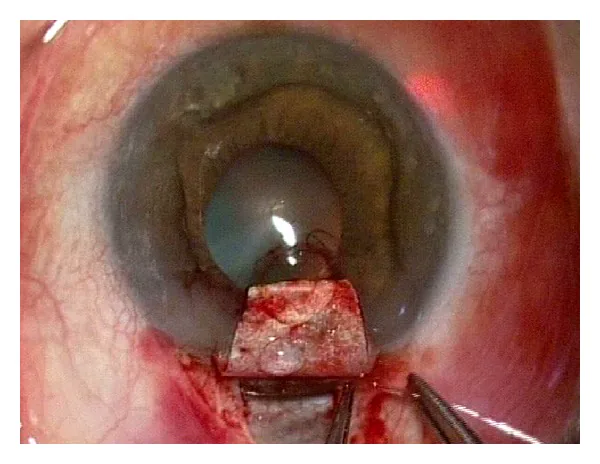

Section titled “4. 手術手技”Ab externo法(従来法)

Section titled “Ab externo法(従来法)”Ab externo法では結膜切開・強膜弁作成の後、シュレム管を露出してマイクロカテーテル(iTrack, Nova Eye Medical)を360°挿入する1)8)。

主な手順は以下の通りである。

- 輪部基部の結膜切開を行う

- 5×5 mmの表層強膜弁を作成する

- 4×4 mmの深層強膜弁を作成し、線維柱帯・デスメ膜窓を露出する

- シュレム管を同定し、光ファイバー付きマイクロカテーテルを360°挿入する

- カテーテル引き抜き時に粘弾性物質(OVD)を注入してシュレム管を拡張する

- 10-0ポリプロピレン(プロレン)縫合糸を管内に留置し、線維柱帯に張力をかける

- 強膜弁を水密に閉鎖する(濾過胞形成を回避する場合)

管内テンション縫合糸はシュレム管の開存維持と線維柱帯への張力付与の二重の効果を持つ9)。